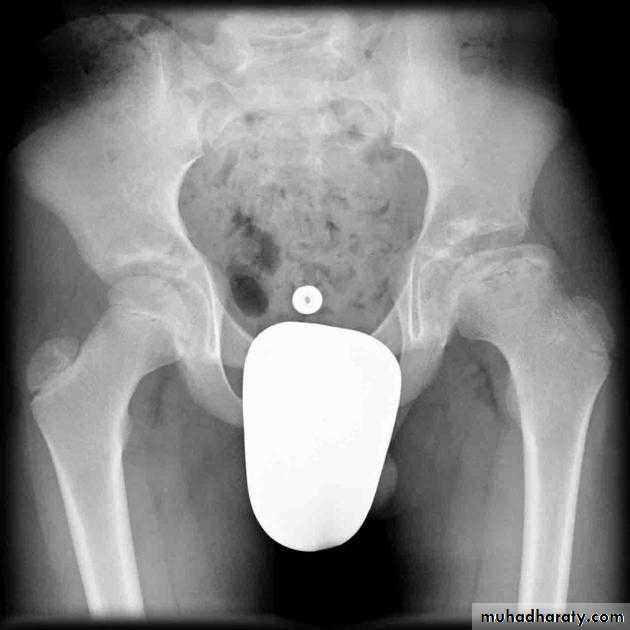

Who can you do Von Rosen view

At 3-6 months :abduction of the thigh 45 degree and internal rotation

Shenton line is drawn along the inferior border of the superior pubic ramus and should continue laterally along the infero medial aspect of the proximal femur as a smooth line. If there is supero lateral migration of the proximal femur due to DDH then this line will be discontinuousPerkin line is drawn intersecting the lateral most aspect of the acetabuler roof & iliac creast

Q…CDH occurs most commonly in ????(70%) in the left hip . Bilateral involvement is seen in 5%

Q…By simple diagram draw pelvis with lines (shenton’s & Perkins line)